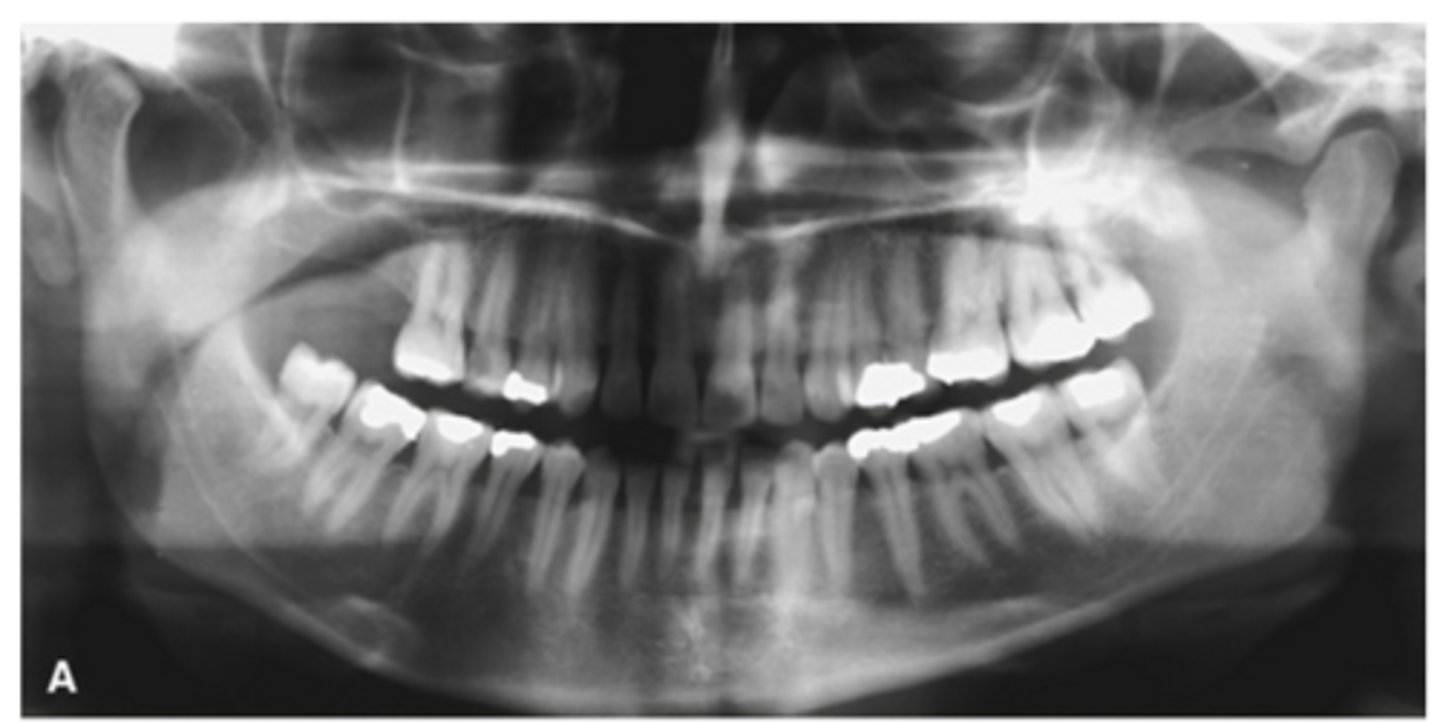

RA (rheumatoid arthritis)

Image A shows a lateral ceph where the patient has a steep mandibular plane and anterior open bite.

Image B shows erosion of the temporal component of the TMJ

What is the diagnosis of the patient based off these radiographs and what are the features?